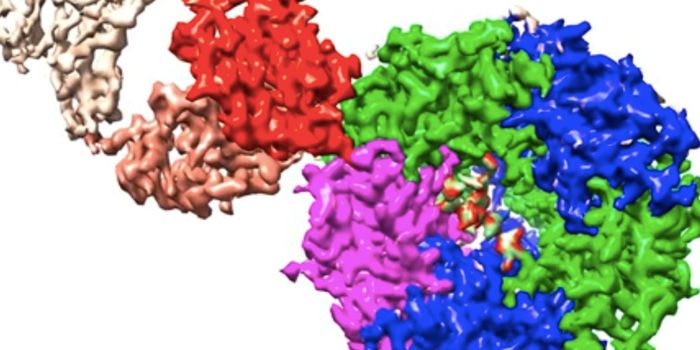

JUL 21, 2022ImmunologyUsing cryo-electron microscopy, researchers captured images of a molecule called an autoantibody as it attached to a rec ...